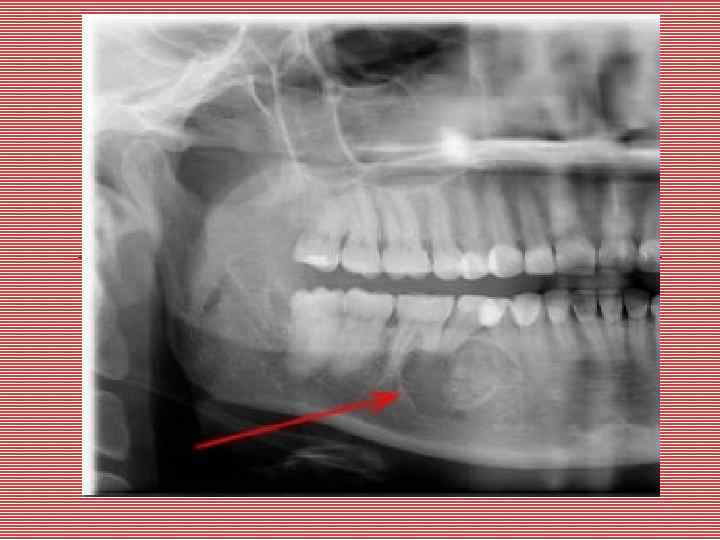

Гигантоклеточная опухоль Гигантокпеточная опухоль (остеокластоиа, остеобластокластома, бурая опухоль). Встречается в 30% случаев от всех опухолей челюстных костей. Чаще возникает у детей и молодых лиц женского пола. Локализация: область иремоляров нижней челюсти, внутрикостно. Растет медленно. Макроскопически: выбухание челюсти с подвижностью и смещением зубов и рассасыванием их корней. Кротикальный слой истончается и разрушается. Представляет собой узел от 2 до 5 см в диаметре, без четких границ, мягкой консистенции, пестрого вида на разрезе за счет чередования участков белесовато-серого цвета с темно-красными, желтоватыми, бурыми. Содержит кисты разной величины с прозрачным содержимым. Микроскопически: клеточно-волокнистая ткань с полями и гнездами опухолевых клеток двух типов: мелких, типа остеобластов, и гигантских многоядерных, типа остеокластов. Сосуды синусоидного типа или очаги «тканевого» кровотока, гемосидероз. Встречаются очаги ксантоматоза и неполноценного остеогенеза. Редко встречается злокачественный аналог гигантоклеточной опухоли, в которой анаплазии подвергаются клетки типа остеобластов.